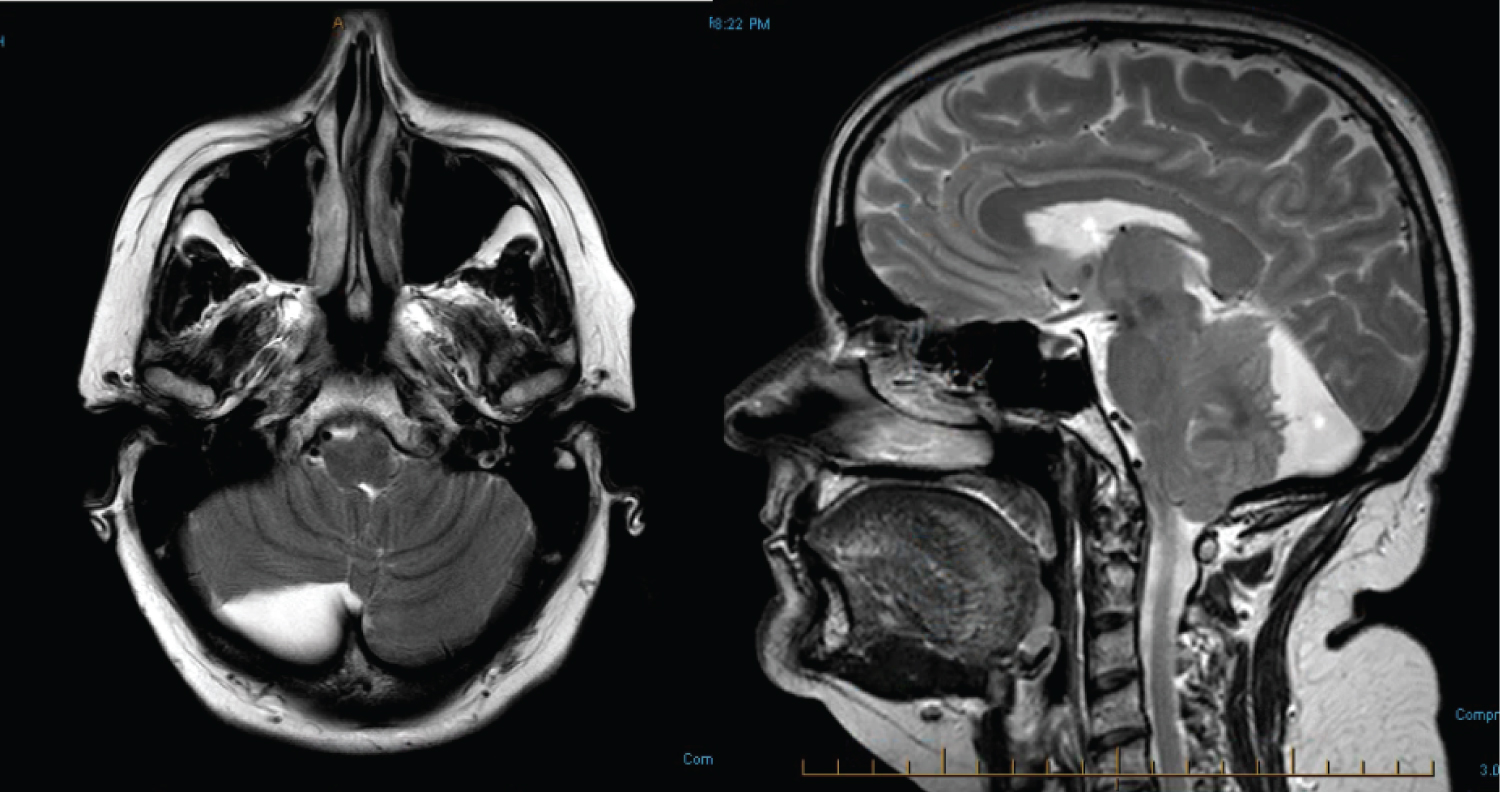

Figure 2: MRI findings showing significant increase in size of the retrocerebellar arachnoid cyst 12 years later.

Figure 2a: T2 weighted axial MR image reveals that the arachnoid cyst now measures 25 mm anteroposterior, 67 mm transversely, 56 mm craniocaudal, with significant mass effect on the posterior fossa structures.

Figure 2b: T2 weighted sagittal MR image showing a 11 mm descent of the right cerebellar tonsil through the foramen magnum. There is transtentorial herniation with some effacement of quadrigeminal cistern. There is supratentorial ventricular dilatation, and periventricular hyperintensity suggesting transependymal CSF seepage. View Figure 2